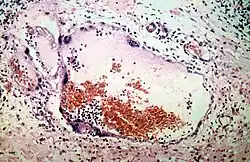

El diagnóstico por laboratorio de esta enfermedad puede realizarse de forma precoz con la técnica PCR, al aislar el virus de muestras tomadas de la garganta, hisopado nasal, líquido cefalorraquídeo, orina y sangre. Los anticuerpos IgG e IgM pueden detectarse de forma más tardía que el material genético viral, la detección de estos anticuerpos suele realizarse con la técnica ELISA. El virus también puede ser aislado con inmunohistoquímica en análisis de autopsia.[5]